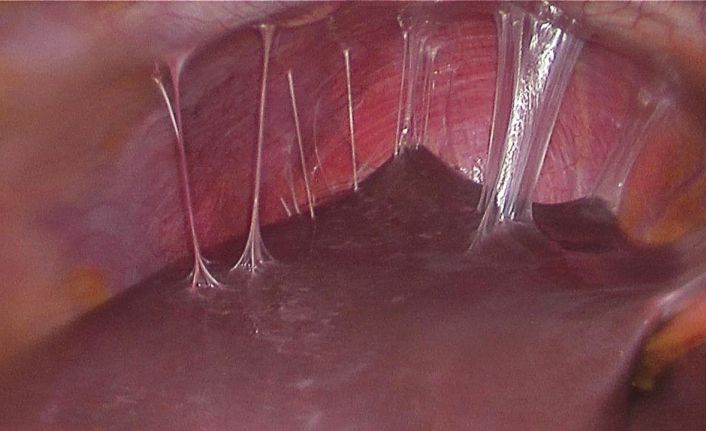

Fıtık onarımının dünya çapında en yaygın cerrahi prosedürlerin başında geldiğine işaret eden Prof. Dr. Esra Karaca, her yıl yaklaşık 20 milyon hastanın fıtık gelişimine bağlı olarak ameliyat edildiğini açıkladı. Karın duvarında oluşan defektin, mesh adı verilen bir tıbbi tekstil materyali implante edilerek onarılmasının da bu alanda yapılan en yaygın cerrahi müdahalelerden birisi olduğunu söyleyen Prof. Dr. Esra Karaca, “Bununla beraber, kullanılan meshler ciddi adezyonlara neden olmaktadır. Daha önce fıtık ameliyatı olmuş hastaların yüzde 90’ından fazlasının ameliyat sonrası adezyon semptomları gösterdiği tespit edilmiştir. Adezyonlar ise kronik karın ağrılarına ve iç organlarda ölümcül tıkanıklıklara yol açabilmektedir. Yeni ürünler denenmesine rağmen, post-operatif adezyon henüz başarıyla önlenememiştir. BUÜ Tıp Fakültesi Hastanesi’nden Türkiye ile ilgili bir projeksiyon yapılarak, ülkemizde bir yılda kullanılan fıtık mesh sayısının 100 bin civarında olduğu sonucuna varılmıştır. Bu nedenle; proje çerçevesinde geliştirilecek başarılı bir kompozit meshin, yurt dışından mesh ithalatını önemli oranda azaltacağı öngörülmektedir” açıklamasında bulundu.

Karaca ayrıca projede, karın fıtıklarının onarımında kullanılmak üzere çörek otu yağı içeren anti-adezyon özellikli nanolifli yüzey ile takviyelendirilmiş PP örme mesh yapıların geliştirilmesi ve kompozit meshlerin fıtık onarımı ve adezyon önleme performansının in vitro ve in vivo çalışmalarıyla değerlendirilmesini hedeflediklerini de sözlerine ekledi.